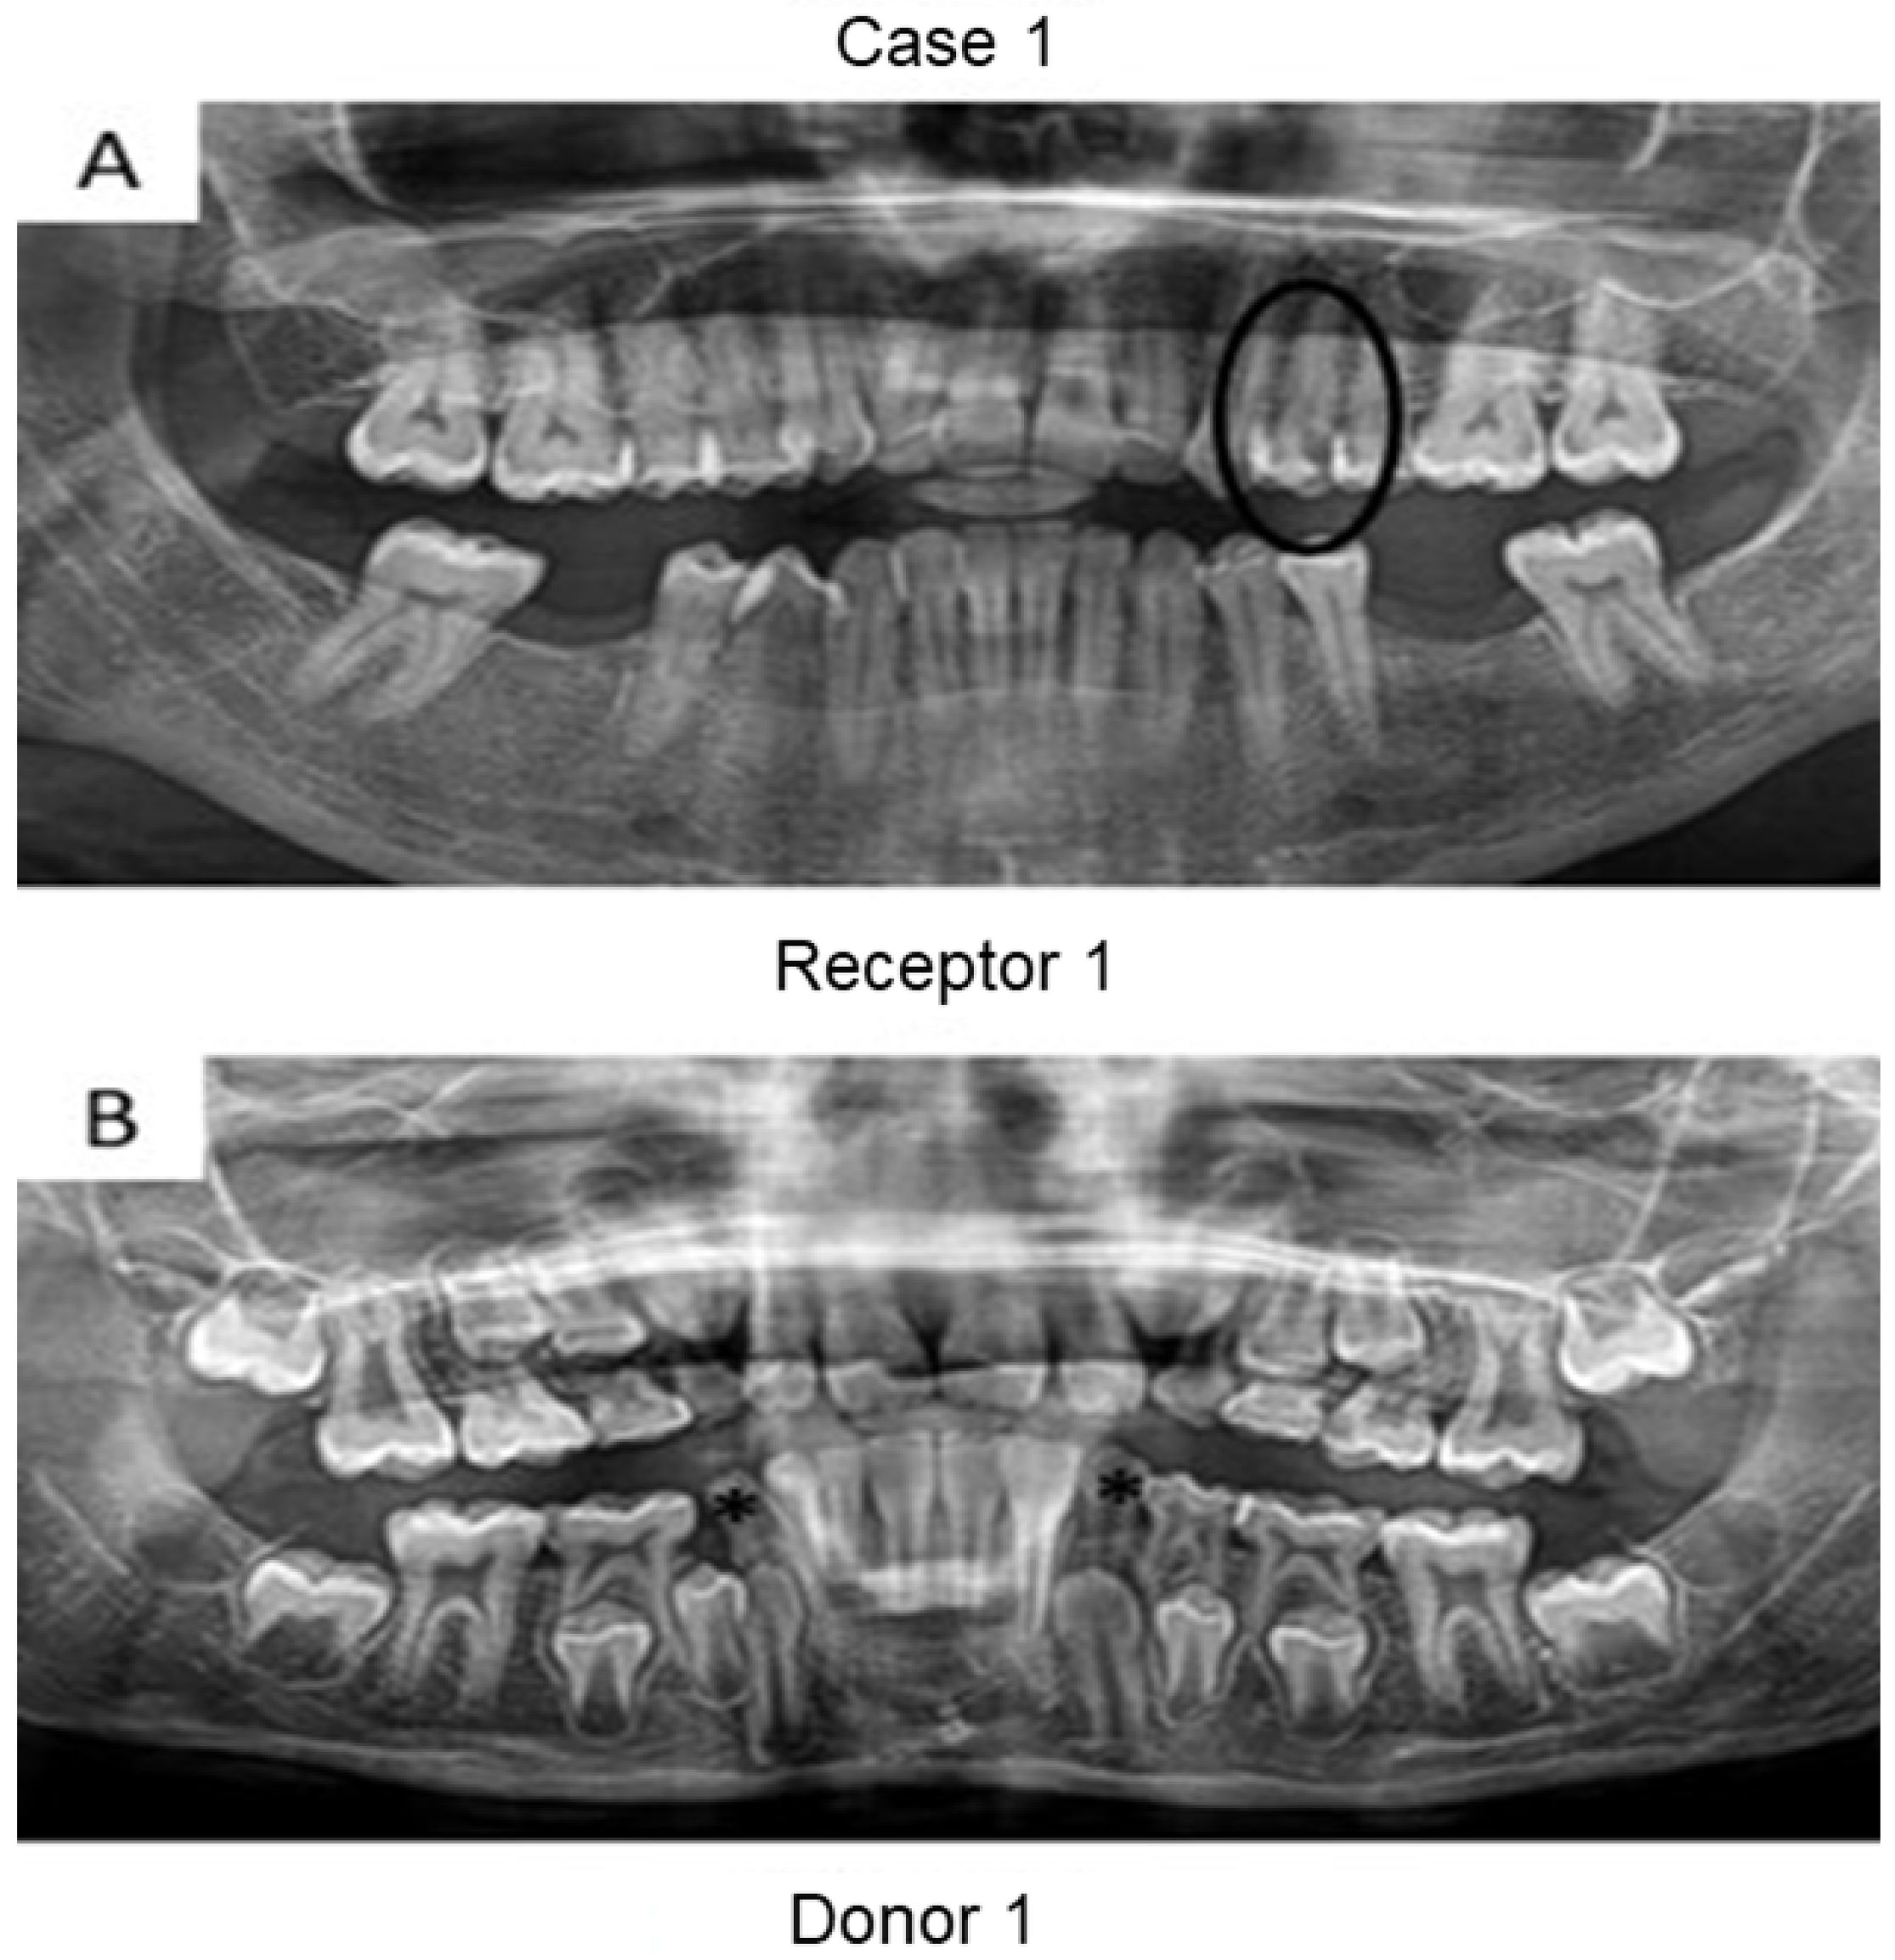

First, panoramic radiography was performed on all patients in the three cases (Figure 1, Figure 2 and Figure 3), as well as computed tomography (CT) scanning with a 0.25 mm voxel size in order to confirm the periapical status of each tooth requiring endodontic treatment. The extraction of teeth from the patients’ children was performed without tooth sectioning and with extreme caution in order to avoid damaging the tooth and the apical structures. The extraction was carried out with local anesthesia using 1.8 mL of 2% lidocaine (1:80,000 epinephrine) through a nerve block technique. The extracted teeth were stored in a sterilized saline solution. At the same time and in the same dental office, the single-root teeth requiring root canal treatment were also anesthetized as aforementioned, isolated with a rubber dam, and pulp chamber access was executed with diamond burs with a high-speed handpiece under continuous and copious water irrigation. The canal instrumentation was performed using rotary files (Wave One Gold, Dentsply, Rio de Janeiro, Brazil) in combination with irrigation using a tri-antibiotic solution (ciprofloxacin, minocycline, and metronidazole at 500 μg/mL each) [14,15]. Prior to the rotary files, one #10 manual K-file (Dentsply) was used to perform the patency. No apical bleeding was performed because it was a different protocol than the revascularization strategy [15,16].

Herein, the primary teeth extracted (asterisks in Figure 1 and Figure 2) were scheduled to be extracted with minimal injury as they were vertically inclined, and permanent teeth were already formed/erupted in cases 1 and 2. Furthermore, the tooth must be stored as soon as possible in a sterilized saline solution; the complete disinfection prior to pulp removal and transplantation is mandatory [21]. The sectioning of the extracted tooth must be performed using a sterilized handpiece and diamond disks only after the root canal instrumentation of the receptor tooth [10]. Pulp should also be removed with sterilized tweezers (Figure 4B) and inserted into the roots of the acceptor teeth using disinfected gutta-percha cones. Indeed, all these procedures may promote minimal contamination during the clinical treatment, thereby increasing the probability to perform bacterial-free endodontic regeneration.

Figure 1. Panoramic radiographs of initial visit of the two patients from case 1. Black circle indicates the tooth requiring root canal treatment (receptor tooth) in the mother whilst the asterisks point to the primary canines in the son with planning for extraction (pulp donator tooth). The pulps from both canines were transplanted to the buccal and palatal canals from the first premolar of the mother.